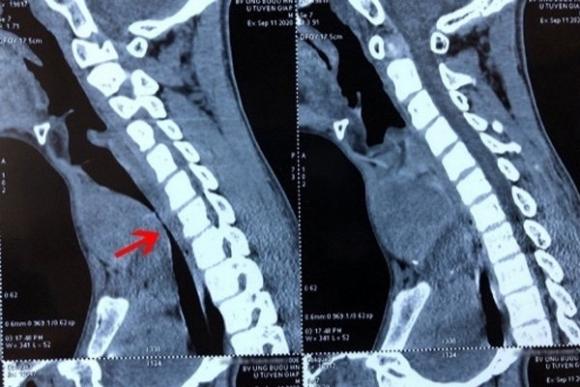

Sai lầm khiến bệnh nhi mắc ung thư tuyến giáp nguy kịch